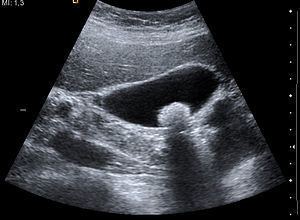

Bu iki kanal karaciğer çıkışında birleşir. Daha sonra bu kanala safra kesesi kanalı da eklenerek koledok kanalı oluşur ve on iki parmak bağırsağına açılır. Bu kanal sistemi içerisinden gelişen her hangi bir kitle, kanallarda genişlemeler yada kistler ultrason inceleme ile saptanabilir. Safra kesesi hastalıkları günümüzde sık görülmektedir. Bu hastalıklardan en sık olanları safra kesesi taşları ve safra kesesi iltihabıdır. Her iki durumda ultrasonda kolaylıkla görülüp bir an önce tedaviye başlanabilir.